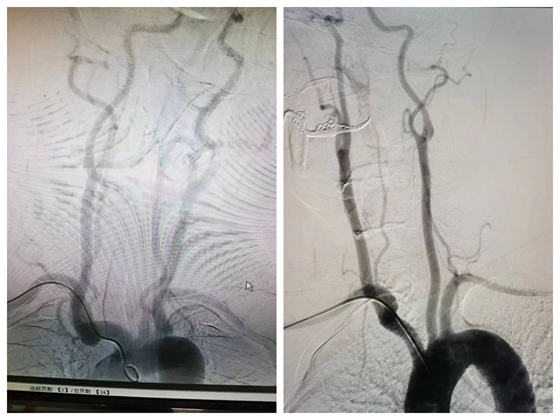

近日,57岁的李先生,因发作性头晕、左侧肢体无力麻木17小时入院,入科后反复短暂性脑缺血(TIA)发作,出现头晕、左侧肢体无力麻木数次,每次发作数分钟后好转,患者及家属非...